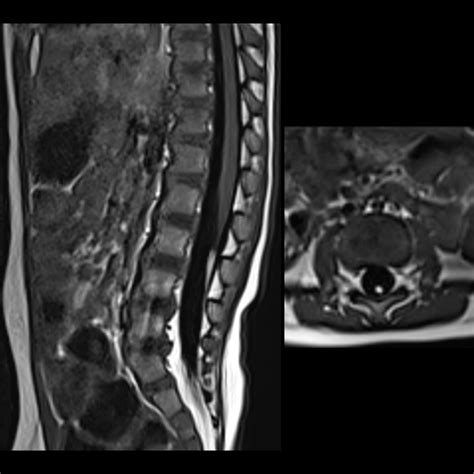

• MRI (Magnetic Resonance Imaging): If the ultrasound is inconclusive, or if the baby is slightly older (as the bones in the lower spine harden, making ultrasound less effective), an MRI may be ordered. This provides a more detailed, high-resolution view of the spine.